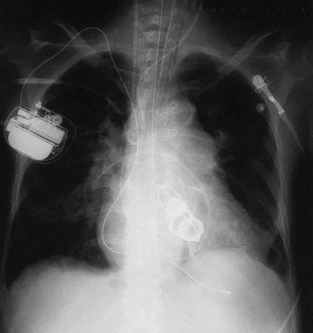

The widest use of X-rays is for imaging objects that are opaque to visible light, such as the human body or aircraft parts. In humans, the risk of cell

The ability of X-rays to penetrate matter depends on density, and so an X-ray image can reveal very detailed density information. Figure 24.20 shows an example of the simplest type of X-ray image, an X-ray shadow on film. The amount of information in a simple X-ray image is impressive, but more

Figure 24.20 This shadow X-ray image shows many interesting features, such as artificial heart valves, a pacemaker, and the wires used to close the sternum. (credit: P. P.

The use of X-ray technology in medicine is called radiology—an established and relatively cheap tool in comparison to more sophisticated

technologies. Consequently, X-rays are widely available and used extensively in medical diagnostics. During World War I, mobile X-ray units,